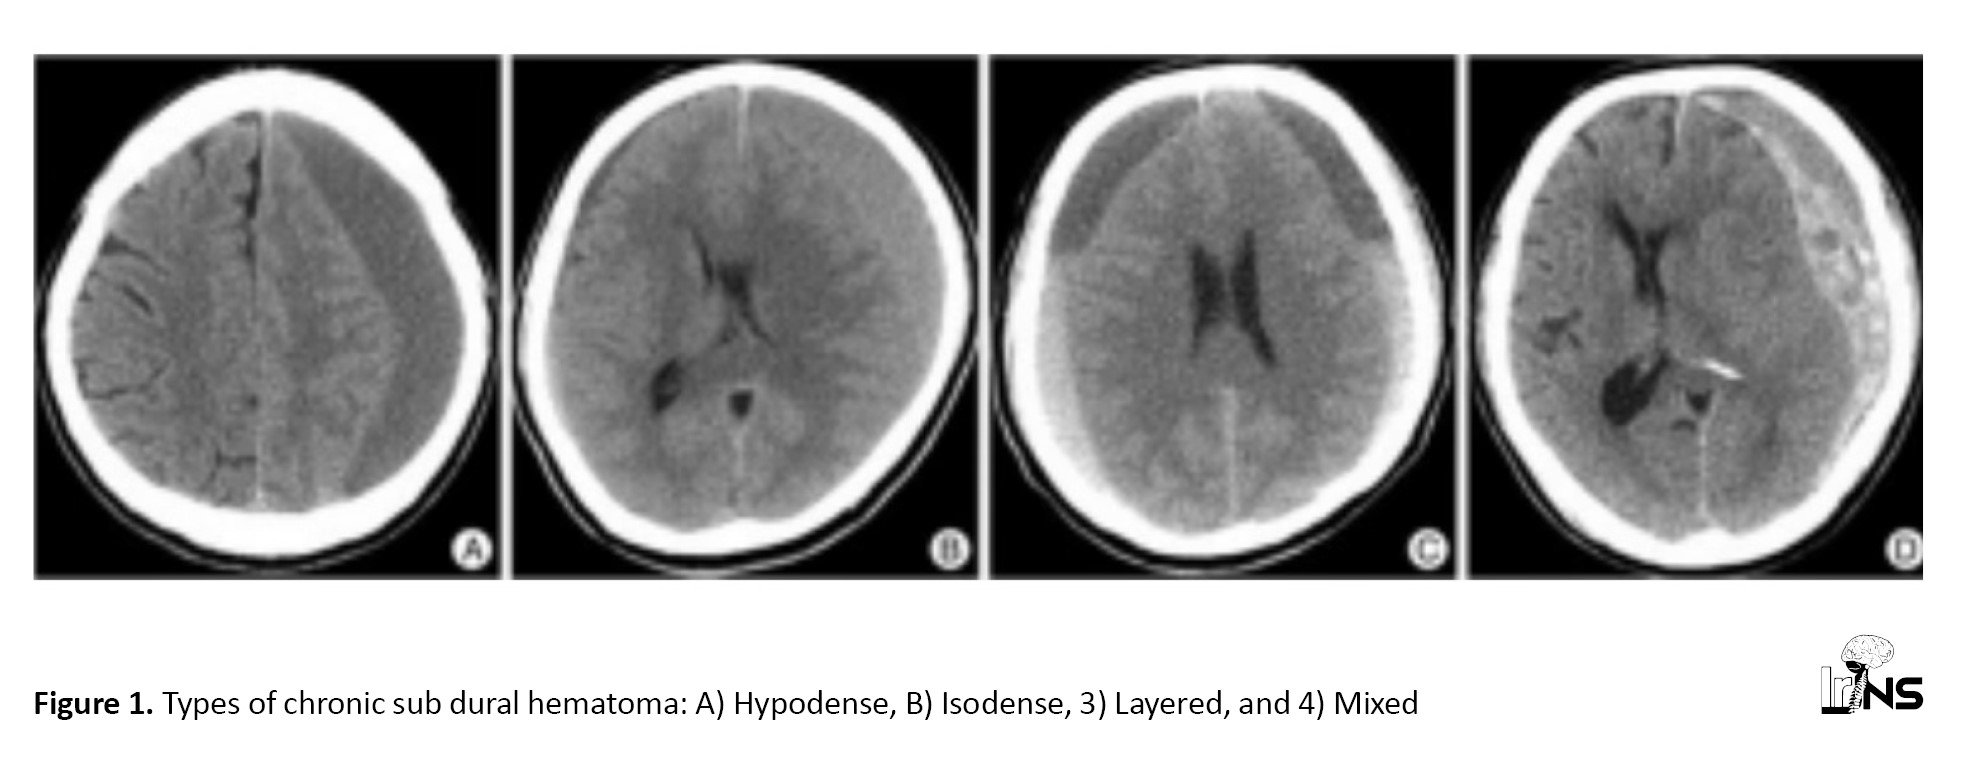

This was a prospective study done in a series of 80 patients who underwent evacuation of CSDH in our center between 2018 and 2020. Patients underwent imaging in the form of a computed tomography (CT) scan and were grouped based on Nomura’s classification [6], which divided CSDH into high density, iso density, low density, layered, and mixed types. We grouped the former three into the homogeneous group and the latter two into a heterogeneous group.

Figure 1 demonstrates the different types of CSDH (

Nomura et al. proposed a system [6] where CSDH was classified based on CT imaging as isodense, hypodense, mixed dense, and layering types of hematoma. They described higher fibrinogen and higher D-dimer levels in the layering and mixed density types of CSDHs compared to the high, iso, and low-density types on CT scans. This was comparable to the findings in the present study, where D-dimer levels were the highest in the mixed group, followed by the Layering type, with the hypodense and isodense groups having lower levels of D-dimer.